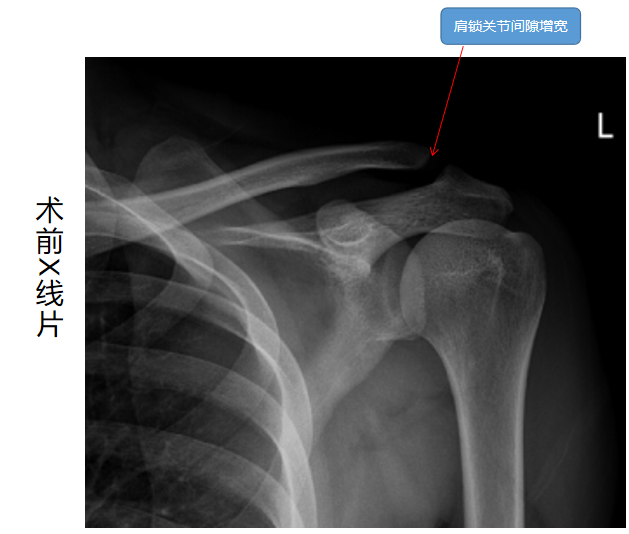

近日,我院骨伤科成功为一名左侧肩锁关节脱位的患者实施全镜下肩锁关节脱位双带袢钢板(双Endobutton钢板)固定术,该例手术在全市尚属首例。这也彰显出我院运动医学的硬实力。 患者王某,男,24岁。因“摔伤致左肩关节疼痛10天”就诊于我院;经查体及辅查后以“左侧肩锁关节脱位”收入我科。查体:左侧肩锁关节压痛,琴键征阳性。辅查:X线片示左侧肩锁关节脱位。

患者外伤后辗转就诊于多家医院,均建议手术治疗,或建议“锁骨钩钢板”固定,或建议“经C臂透视喙突钻骨道袢钢板”固定,但传统锁骨钩钢板后易出现肩峰刺激致肩关节活动受限、肩痛,且需再次手术取出内固定物,而且会发生可能术后再脱位等术后并发症;而对于经C臂透视定位喙突钻骨道袢钢板固定术,在钻取骨道时因为是“盲钻”,血管神经损伤风险较高,且喙突钻骨道后可能出现骨道劈裂甚至继发性骨折等。入院后骨伤科运动馆医学组积极组织讨论,分析各种手术利弊,结合科室关节镜手术优势,决定为患者施行全镜下肩锁关节脱位双带袢钢板(双Endobutton钢板)固定术。该术式在关节镜直视下既可探查关节内情况,直视下钻取锁骨骨道避免血管神经损伤,袢钢板固定时线带是环绕喙突基底部而不经喙突钻骨道,避免喙突骨道劈裂甚至继发性骨折等。术中,肖欢副主任医师及周建军主治医师紧密配合,按既定手术方案为患者施行手术,经过短短的2小时后,手术成功。患者手术后第2天顺利出院。